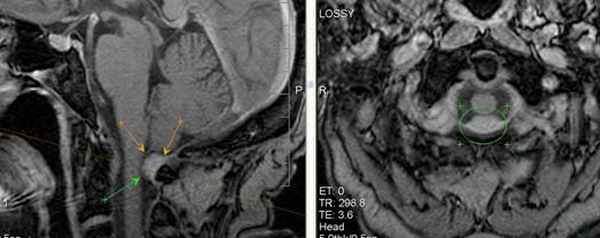

Подобная аномалия представляет собой дорсальную компрессию спинного мозга в сегменте между 1 и 2 шейными позвонками, приводящая к цервикальной сирингомиелии при значительно выраженном сдавлении. Аномальное утолщение желтой связки в купе с твердой мозговой оболочкой формирует дурально-фиброзный тяж, компримирующий нервные структуры. Лимфоцитарное воспаление дурально-фиброзного тяжа может вызывать различные степени сжатия от умеренного – компрессии только подпаутинного пространства до значимого сдавления ткани спинного мозга. Причина возникновения дурально-фиброзного тяжа до сих пор неизвестна. Однако считается что немаловажную роль в ее формировании отводится патологическая сублюксация в атланто-аксиальном или (и) в атланто-окципитальном комплексе.

Мрт пациента с краниоцервикальной мальформацией (Впадина Дьюи, сирингомиелия в шейном отделе)

Впадина Dewey. Интраоперационный рентген.